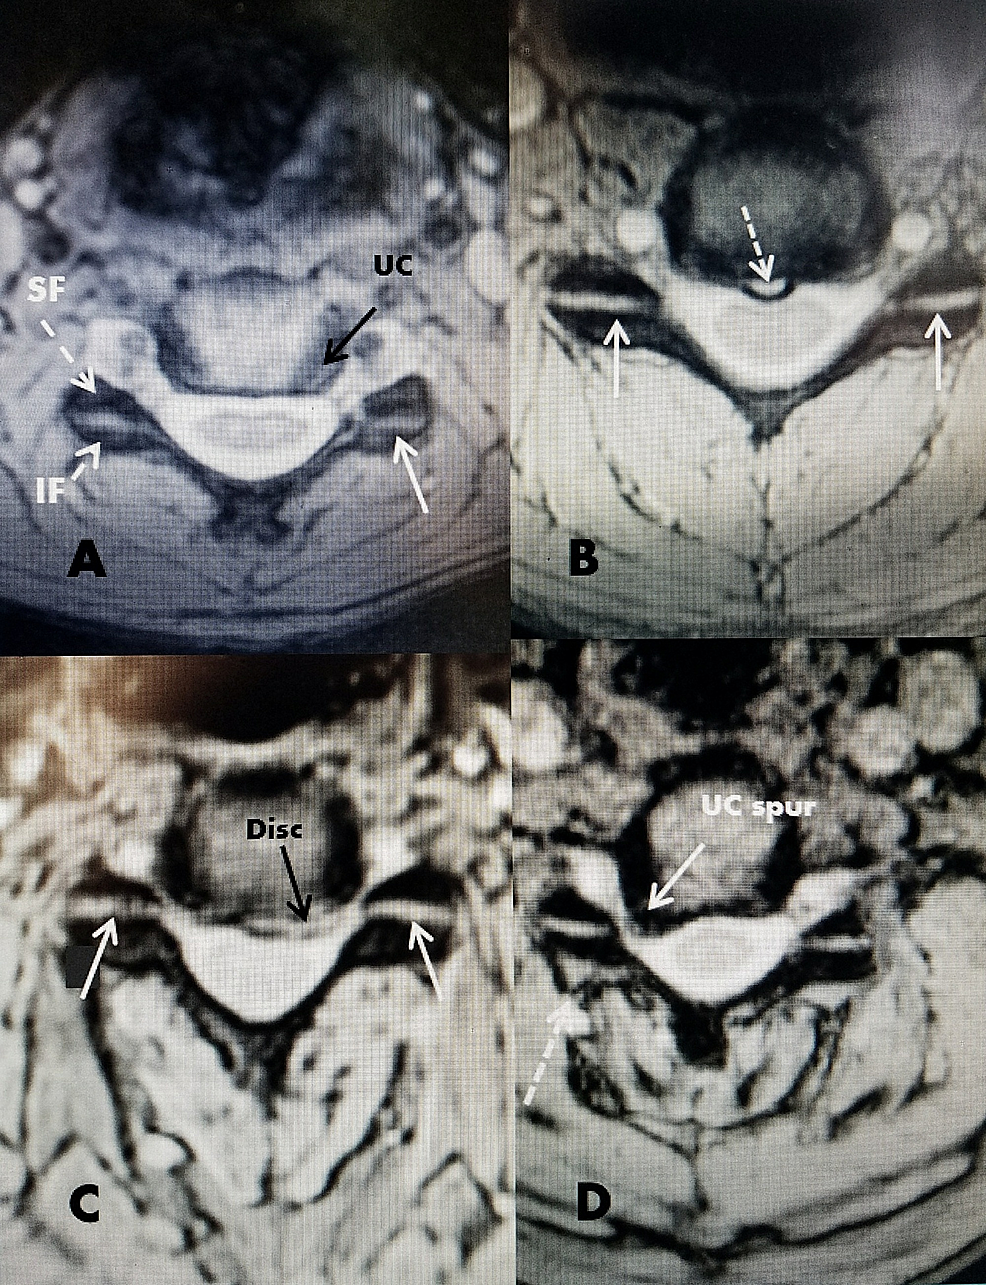

From www.cureus.com

Cureus Direct Posterior Bipolar Cervical Facet Radiofrequency Facet Joint Rhizotomy (this is sometimes referred to as nerve ablation.) Explore rhizotomy, a targeted procedure for chronic back pain offering relief for 9 months to 3+ years. This surgery uses chemicals or an electrical current to destroy nerve fibers that send pain signals to the brain. Information to help patients prepare for a facet rhizotomy and what to expect after the. Rhizotomy. Facet Joint Rhizotomy.

Cureus Direct Posterior Bipolar Cervical Facet Radiofrequency Facet Joint Rhizotomy The procedure for these issues is called facet rhizotomy, as it involves the nerves traveling through the facet joints of the spine. Facet rhizotomy is a pain management treatment option used for chronic pain. Rhizotomy surgery (also called radiofrequency ablation) may be considered to target the nerve roots that pass through the facet joints. An rfa procedure is commonly used. Facet Joint Rhizotomy.

Cureus Direct Posterior Bipolar Cervical Facet Radiofrequency Facet Joint Rhizotomy Facet rhizotomy is a pain management treatment option used for chronic pain. An rfa procedure is commonly used to target and disrupt the small medial branch nerves responsible for transmitting pain signals from facet joints, which are connections between bones in the spine. (this is sometimes referred to as nerve ablation.) Rhizotomy surgery (also called radiofrequency ablation) may be considered. Facet Joint Rhizotomy.